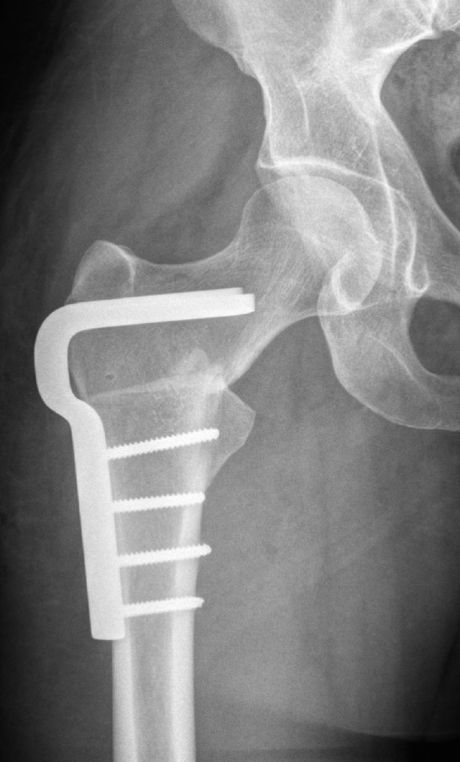

Die häufigst durchgeführte Technik der Proximalen Femur Osteotomie geschieht mittels chirurgischem Zugang von der Außenseite des Oberschenkel. Nach Durchtrennung des Knochens und Neupositionierung in der gewünschten Position wird die erzielte Korrektur mittels Schrauben-Platten-System gehalten, ähnlich wie bei einem Knochenbruch.

Intertrochantäre Ostetomie